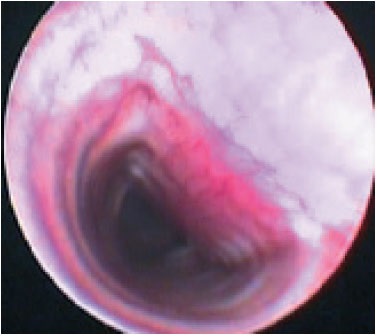

Diagnózis lehet eredményeként X-sugarak a betegek az oldalsó fekvő helyzetben. Fluoroszkópiát jobb a diagnosztikus értékű, mint a röntgenfelvételek, mivel Ez lehetővé teszi láthatóvá a légcső mozgásban alatt lélegzik. Ha ez nem lehetséges, hogy végezzen röntgen, szükség van a kellően pontosan megragadni a pillanatot belélegzés vagy kilégzés a röntgenfelvételen. X-sugarak a cervicalis trachea osztályának hajtja végre, amikor az inhalációs, mellkasi tracheális osztály - idején lejárati. A nehéz betegek röntgen végezhető álló oldalsó pozícióban (ris.1,2).

Endoszkópia a legjobb diagnosztikai értékeléséhez a légcső és a hörgők, de végrehajtására csak érzéstelenítéssel. Bronchoszkópia lehetővé teszi, hogy belsejében a légcső az egész hosszában, hogy értékelje az állam az nyálkahártya, hogy értékelje a mozgás a légcső során légzési ciklust. Tracheoscopy „arany standard” diagnózis és használják megerősíteni a diagnózist. A jelenléte a változások a lumen a légcső és a hörgők 4 fok trachea összeomlása. A légcsövet a „normális” van egy csaknem kör alakú annak teljes hossza mentén. Az egészséges állatok légcső áll sobraznyh alakú porcos gyűrűk egymáshoz háti légcső membrán. Dorsalis tracheális membrán általában tekinteni, mint a hosszanti simaizom rossz szakaszok során lélegzik. A légcsövet borított nyálkahártya, amelyeket át nézve a porcos gyűrűk. Nyálkahártya „OK” úgy néz ki, sima, halvány rózsaszín, nyálkahártya alatti réteg gazdag áthatja kapillárisok (3. ábra). Ha a szint 1 tracheális összeomlása is megfigyelhető, hogy az alak a légcső alig változott, dorzális membrán enyhén laza, a porc gyűrűk alátámasztó normális formában légcső, a légcső lumen csökken mintegy 25% (4. ábra). Amikor a 2. fokú összeomlás dorzális membrán kifeszített és laza, kissé lapított porcos gyűrűk, tracheális lumen 50% -kal csökken (5. ábra). Összecsukása 3. fokozatú azzal jellemezve, hogy a dorzális membrán laza úgy, hogy szinte érinti a dorzális a porc gyűrűk porcos gyűrűk dorsoventrally lapított, tracheális lumen csökken 75% (6. ábra). 4. fokú összeomlása a légcső: dorzális membrán fekszik a porcos gyűrűk légcsőgyűrűket lapított és telepített gyakorlatilag nem légcső lumen (7. ábra) (a Tangner CH, Hobson HP: Egy retrospektív vizsgálatban 20 kezelt esetek összeesett légcső / Vet Surg 11: 146, 1982).